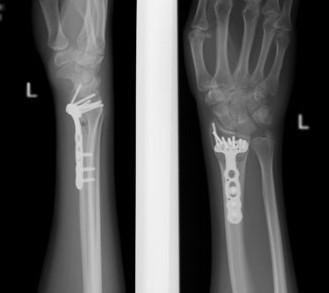

При значительном смещении отломков используется остеосинтез лучевой кости металлической пластиной, специально разработанной для данной области. После сопоставления отломков, пластина фиксируется винтами к поврежденной кости. После установки пластины, на кожу накладываются швы, также применяется гипсовая лонгета.

После хирургического вмешательства назначается медикаментозное лечение: включающие обезболивающие средства, препараты кальция для улучшения срастания кости, а при необходимости — местные препараты для уменьшения отечности. Средняя продолжительность пребывания в стационаре составляет 7 дней. Швы снимают через 2 недели на контрольном приеме у травматолога, тогда же пациенту могут отменить гипсовую повязку. Рука должна оставаться в приподнятом положении на косыночной повязке. Обычно не требуется удаление пластины.